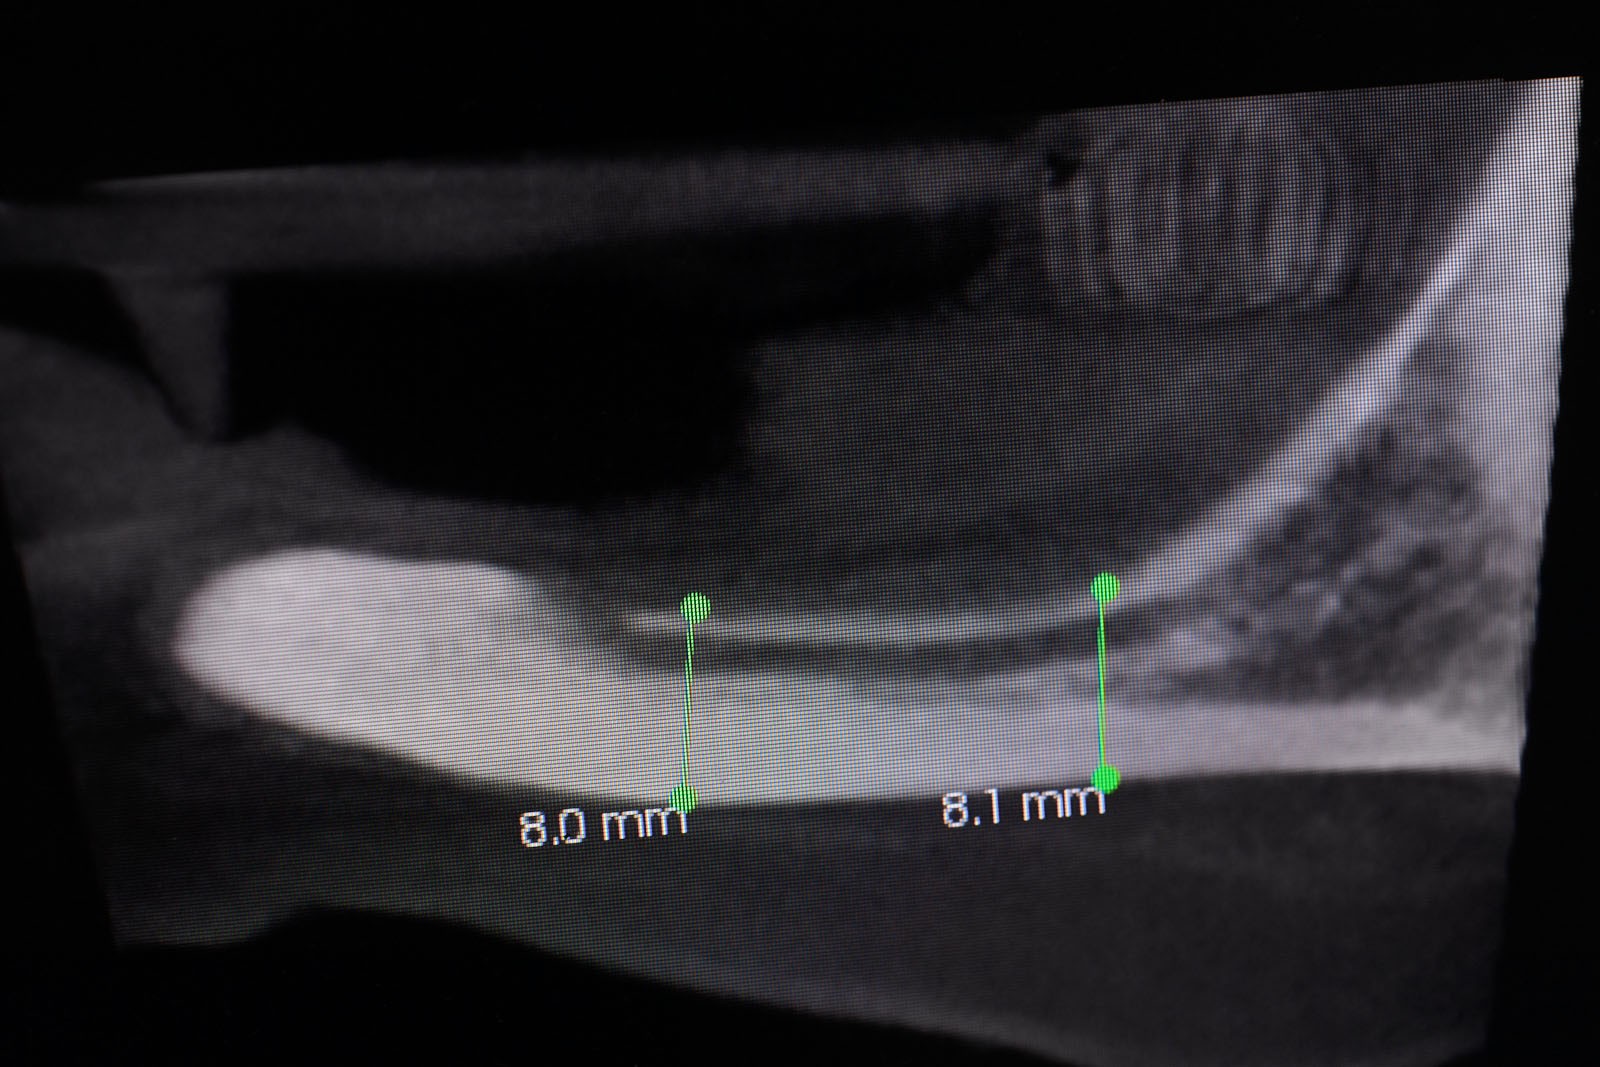

Przed podjęciem leczenia należy określić stopień zaniku kości szczęk oraz żuchwy. W tym celu przeprowadza się badanie kliniczne oraz odpowiednią diagnostykę obrazową pacjenta. Uwzględnia ona zdjęcie panoramiczne OPG jako podstawę dwuwymiarowego obrazowania podłoża kostnego oraz możliwe jest badanie tomograficzne CT lub bardziej precyzyjna tomografia stożkowa CBCT. Opcjonalnie wykorzystywana diagnostycznie tomografia pozwala na bardziej wnikliwą ocenę stopnia zaniku kości w trójwymiarowym, przestrzennym obrazie.

Zatoki szczękowe to symetrycznie umieszczone w kościach szczęk przestrzenie powietrzne, posiadające komunikację z jamą nosa. Średnio pojemność zatok wynosi 24 cm3, a ściany wyścielone są błoną śluzową (membrana Schneidera). Dno zatoki szczękowej stanowi wyrostek zębodołowy, w którym umieszczone są zęby, często zlokalizowane tuż pod cienką wyściółką zatoki. Statystycznie najwęższy obszar kostny w tej strefie zlokalizowany jest na wysokości zębodołów pierwszego i drugiego zęba trzonowego.

• Metoda otwarta – opisana w 1980 przez Jamesa i Boyna – polega na chirurgicznym dostępie do zatoki szczękowej poprzez jej boczną ścianę, następnie delikatnej preparacji, oddzieleniu wyściółki (błony Schneidera) bez jej perforacji, umieszczeniu pomiędzy nią a dnem zatoki materiału odbudowującego kość. Zabieg podniesienia dna zatoki szczękowej może przebiegać z jednoczesnym wszczepieniem implantów lub wszczepieniem ich w czasie odroczonym o 6–8 miesięcy. Warunkiem jednoczesnego wszczepienia implantów jest możliwość pierwotnie stabilnego ich umocowania w pozostałej własnej kości wyrostka zębodołowego. Najmniejsza jej ilość wg niektórych autorów to 1 mm.

• Metoda zamknięta – opisana w 1994 przez Summersa – bez szerokiego otwierania zatoki szczękowej, stosowana w sytuacjach wymagających niewielkiego zakresu rekonstrukcji na wysokość. W tej metodzie materiał regeneracyjny do odbudowy kości wprowadza się przez nawiercony kanał, komunikujący się z zatoką w pozycji zaplanowanej do wszczepienia implantu, lub tylko kondensuje się (zagęszcza, rozpycha i wydłuża) obszar kości dla uzyskania stosownej jej ilości i gęstości dla stabilnego umocowania implantu. Zabieg odbudowy kostnej wg Summersa wykonuje się przy użyciu specjalnego instrumentarium – zestawu osteotomów. Uzyskuje się dodatkowo 2–4 mm kości na wysokość